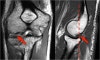

1. Pseudodefect of the capitellum

Pseudodefect of capitellum refers to an abrupt contour change of the posterolateral margin of capitellum on coronal sections and is a potential MRI imaging pitfall giving rise to misinterpretations.

It occurs because the width of the articular surface of the capitellum is non-uniform and gradually tapers posteroinferiorly.